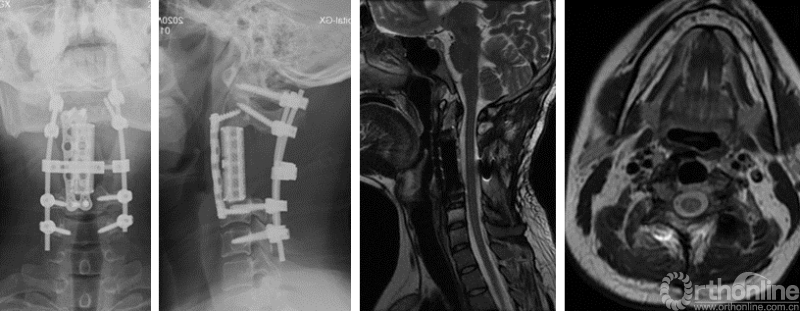

图6,整块切除的C3-C4椎体及肿瘤及标本的X片

手术按计划历时8小时顺利完成,C3-C4椎体及椎旁的肿瘤获得整块切除,过程中肿瘤包膜没有破损。术后病人神志清晰,四肢活动良好。但出现双侧膈肌麻痹,左侧膈肌麻痹是由于术中切断了左侧C3和C4神经根,右侧膈肌麻痹则可能是手术过程中的神经牵拉损伤。

在病人以及ICU和康复科医生的共同努力下,病人终于在术后第22天脱离呼吸机,转入康复科进行了一个月的呼吸康复后顺利出院。之后病人进行了颈椎局部的放疗和术后的化疗。现在已经术后整整一年了,肿瘤没有复发,病人完全正常的生活。